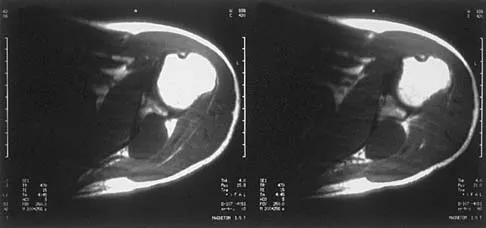

A 17-year-old boy has had a mass in his right thigh for the past 6 months. He denies any history of trauma. Examination reveals that the mass is painless and firm. A radiograph and axial MRI scan are shown in Figures 49a and 49b. What is the most likely diagnosis?